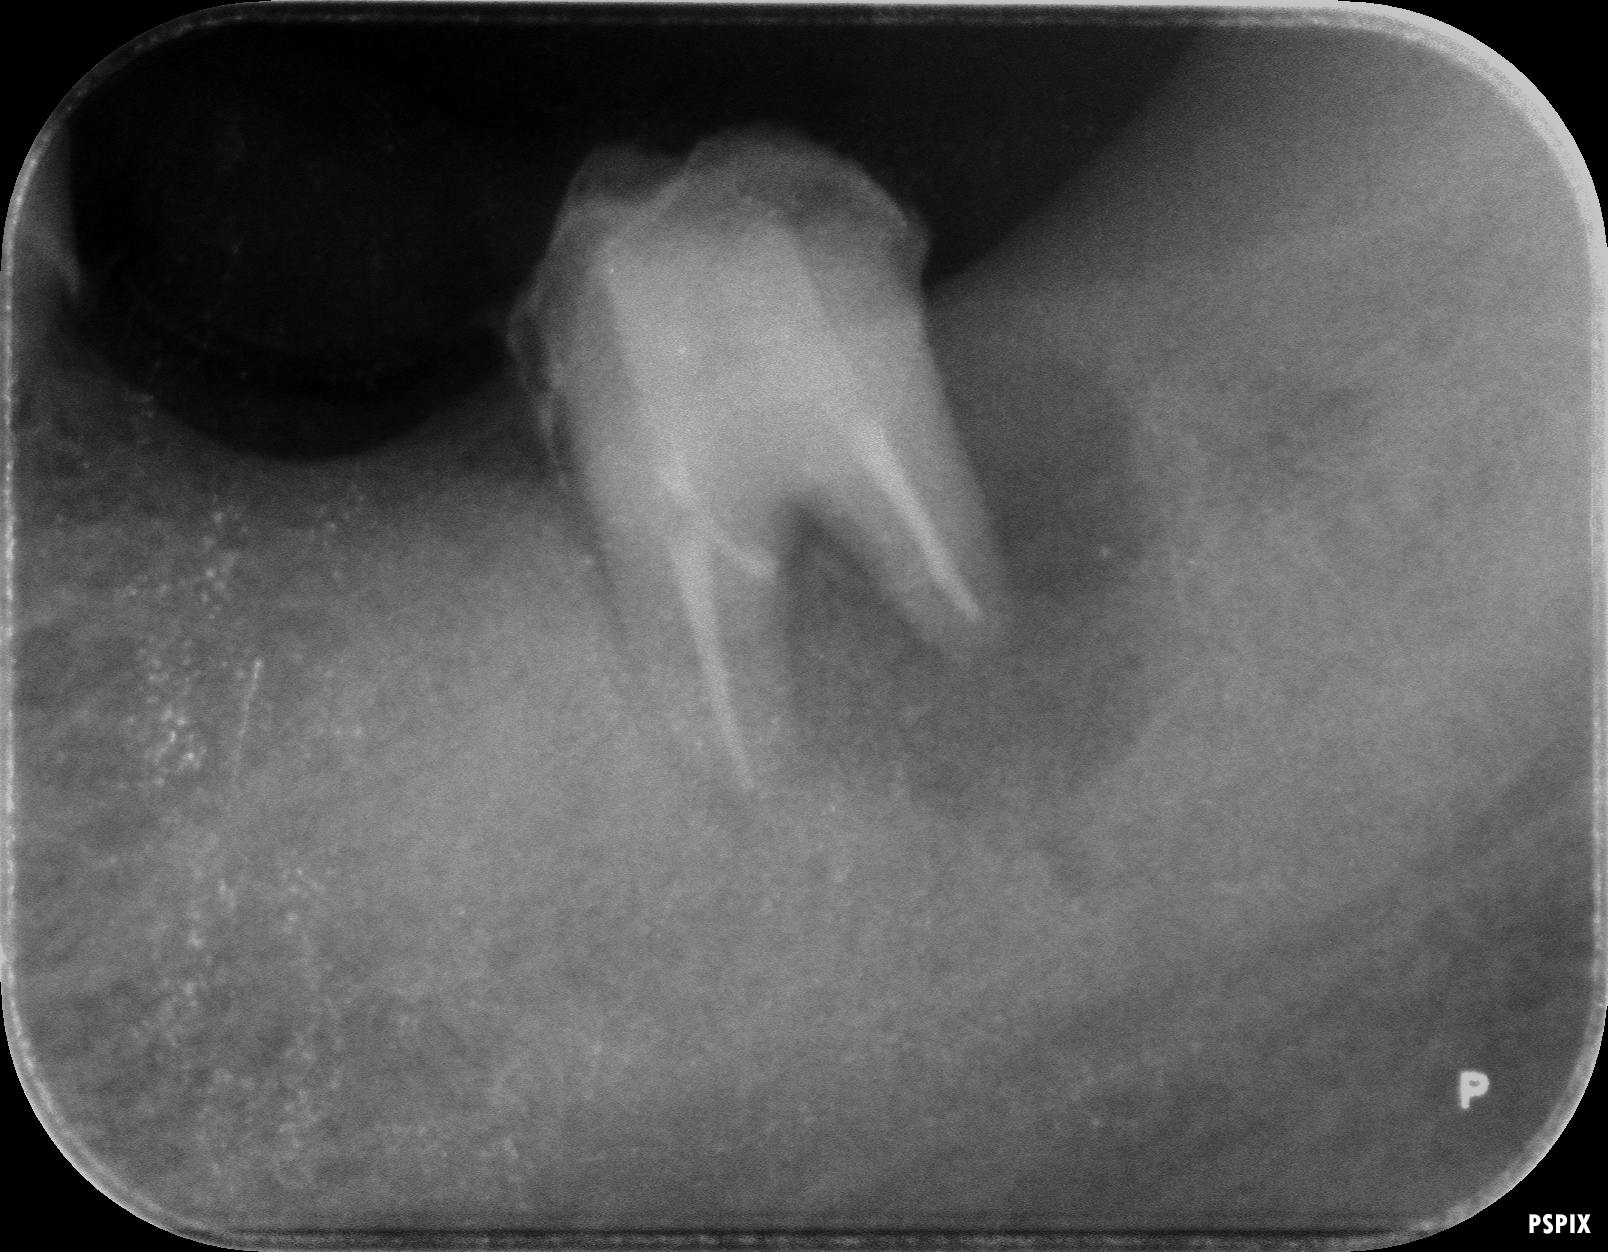

術前のレントゲン写真です。歯の周りに黒い像がありますが骨の吸収像です。

再植術後のレントゲンがこちらです。歯の周りの骨が大分黒くなっています。この状態が骨が無い状態です。